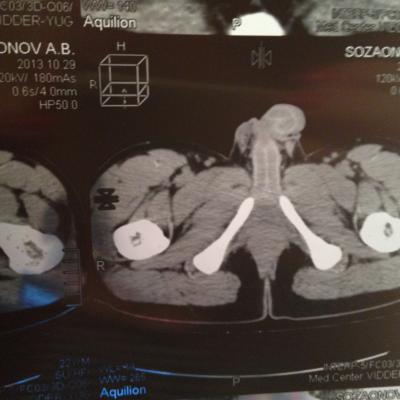

проведена МСКТ области таза!Внеорганных дополнительных патологических образований,лимфаденопатии или свободной жидкости в области таза не выявлено.

Мочевой пузырь-наполнен,стенки не утолщенны,паравезикально-без грубой органки.

Граница между предстательной железой и пузырем несколько четкая,контур пузыря на данном уровне не деформирован.

Предстательная железа-без грубой органики,еденичные микрокальцинаты.

Семенные пузырьки-конфигурация не совсем типична,примерный размер правого 26*28мм.Отмечаются признаки кистовидной трансформации и микрокальцинации обоих пузырьков.Наибольшая из кист слева достигает 9 мм.Обращает на себя внимание неравномерная кальцинация стенок крупных регионарных(текстикулярных)артерий с обоих сторон.

Костно-деструктивных изменений характерных для mts со стороны костей таза не отмечено.

Параректальная клетчатка-не изменена,патологически увеличенных лимфоузлов в параректальном пространстве не отмечено.M.m.levator ani-без особенностей.

Заключение:на момент исследования,КТ-данных за наличие внеорганных дополнительных патологических образований,лимфоденопатии или свободной жидкости в области таза не выявлено.КТ-признаки в пользу проявлений калькулезного везикулита с элементами кистовидной трансформации семенных пузырьков.